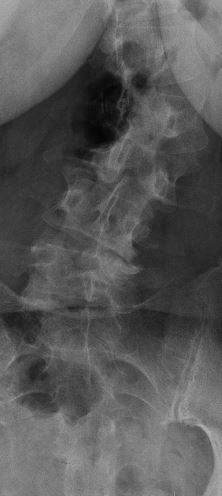

i am the bionic woman, iron woman, titanium broad, i don't know quite yet hopefully i don't break any of the rods or pull any screws...but heres the before and after xrays....

before: lateral scoliosis

lumbar spine 1 scoliosis.JPG

and rotatory scoliosis

right bending.JPG

with bad discs and bone spurs

i am pretty darned close to 0 degrees on the scoliosis!!!! and my spine isn't twisted anymore either! it feels totally different to walk, sit, stand, basically to do anything, but that's okay! the square things in the after xrays are cages to replace the discs that were removed.

been doing all my wussy stretching exercises....still feeling really timid and tender around L2, which is the one that is worst off to the left side in the first xray. they really had to crank that one back into position. i also met some very very happy medical students LOL. they thought it was "so cool and totally awesome" (quote-scary enough) that they could see a laminectomy and help put me back together again (apparently everything twisted and they needed hands to hold things in place so they're stop twisting.....um. LOL.

so they removed the backs off the vertebrae at L2 L3 L4 and L5 it looks like from the xrays. took out all the facet joints (the bars are where they would be)....so that freed up all the pinched nerve roots and took the pressure off my spinal cord.